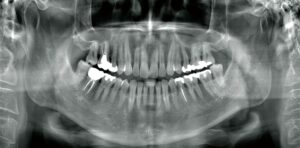

【パノラマ画像(例)】

お口全体の状況を把握できます。